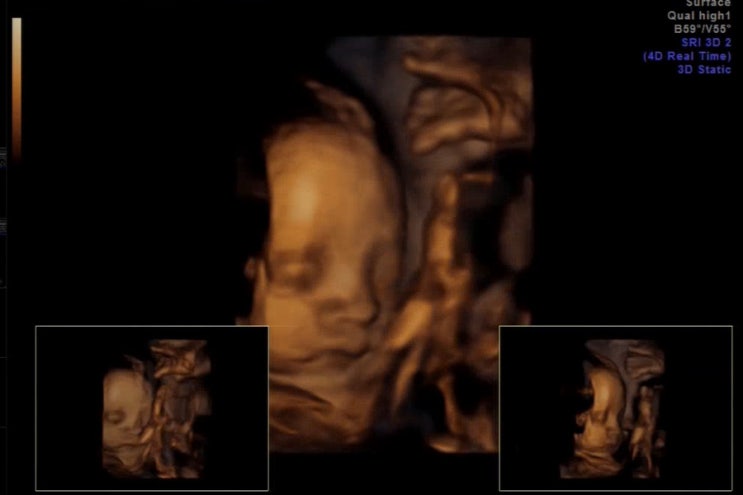

??우리 아기천사 열무모음집! 용띠맘 아들맘 26주 2일차까지 기록